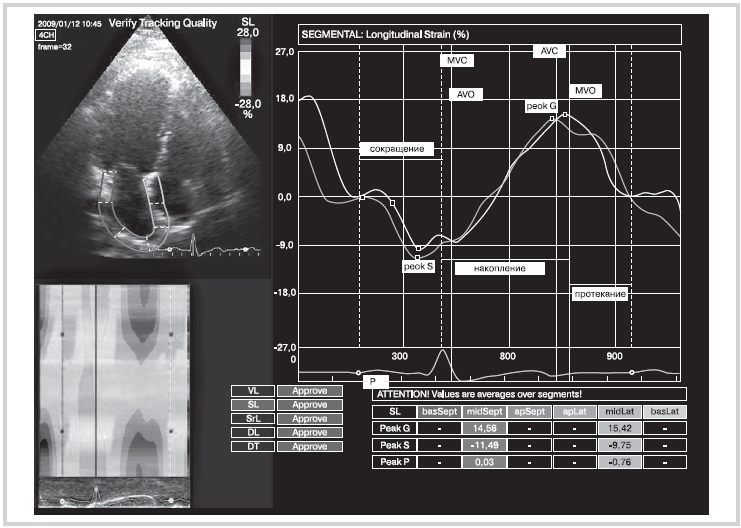

На рисунке приведен пример графической кривой деформации миокарда (ε) ЛП, на котором можно увидеть, как в зависимости от фазы предсердий меняется деформация миокарда, а также максимальные значения этой деформации. В фазу сокращения происходит укорочение миокарда, что отражается на графике в виде деформации с отрицательным значением. Пиковую деформацию (peak S) измеряли как максимальную деформацию до закрытия МК. В фазу накопления миокард предсердия начинает удлиняться и на графике в этот период можно наблюдать переход деформации из отрицательных значений в положительные. Пиковую деформацию (peak G) измеряли как максимальную деформацию в период времени до закрытия аортального клапана. В фазу протекания миокард предсердия снова начинает укорачиваться и перед фазой сокращения (перед началом зубца Р на ЭКГ) значение деформации практически приближается к 0, что, вероятно, свидетельствует об отсутствии деформации в этот период.

Рисунок. Графики продольной деформации (ε) МЖП (нижняя кривая) и боковой стенки ЛП (верхняя кривая) в 4 камерной проекции.

МЖП — межжелудочковая перегородка; MVC — закрытие митрального клапана; АVO — открытие аортального клапана; AVC — закрытие аортального клапана; MVO — открытие митрального клапана; peak G — максимальная деформация в фазу наполнения (%); peak S — максимальная деформация в фазу сокращения (%).